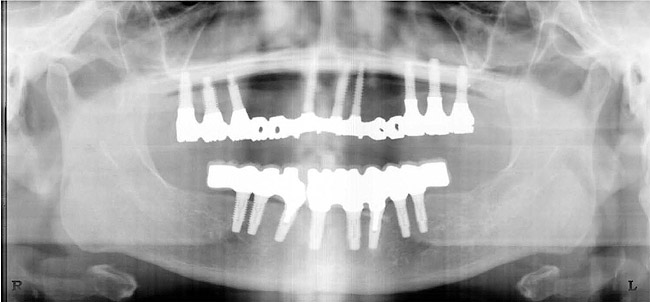

Figure 3   A crown height space < 15 mm necessitates a PFM material selection.

Figure 3

Figure 4  A crown height space > 15 mm necessitates a hybrid restoration.

Figure 4

Figure 5  The increased amount of metal required for this prosthesis greatly increases the laboratory costs.

Figure 5

Figure 6  The increased amount of metal required for this prosthesis greatly increases the laboratory costs.

Figure 6

Figure 7   A hybrid restoration requires less metal to fabricate.

Figure 7

Figure 8   A hybrid restoration requires less metal to fabricate.

Figure 8